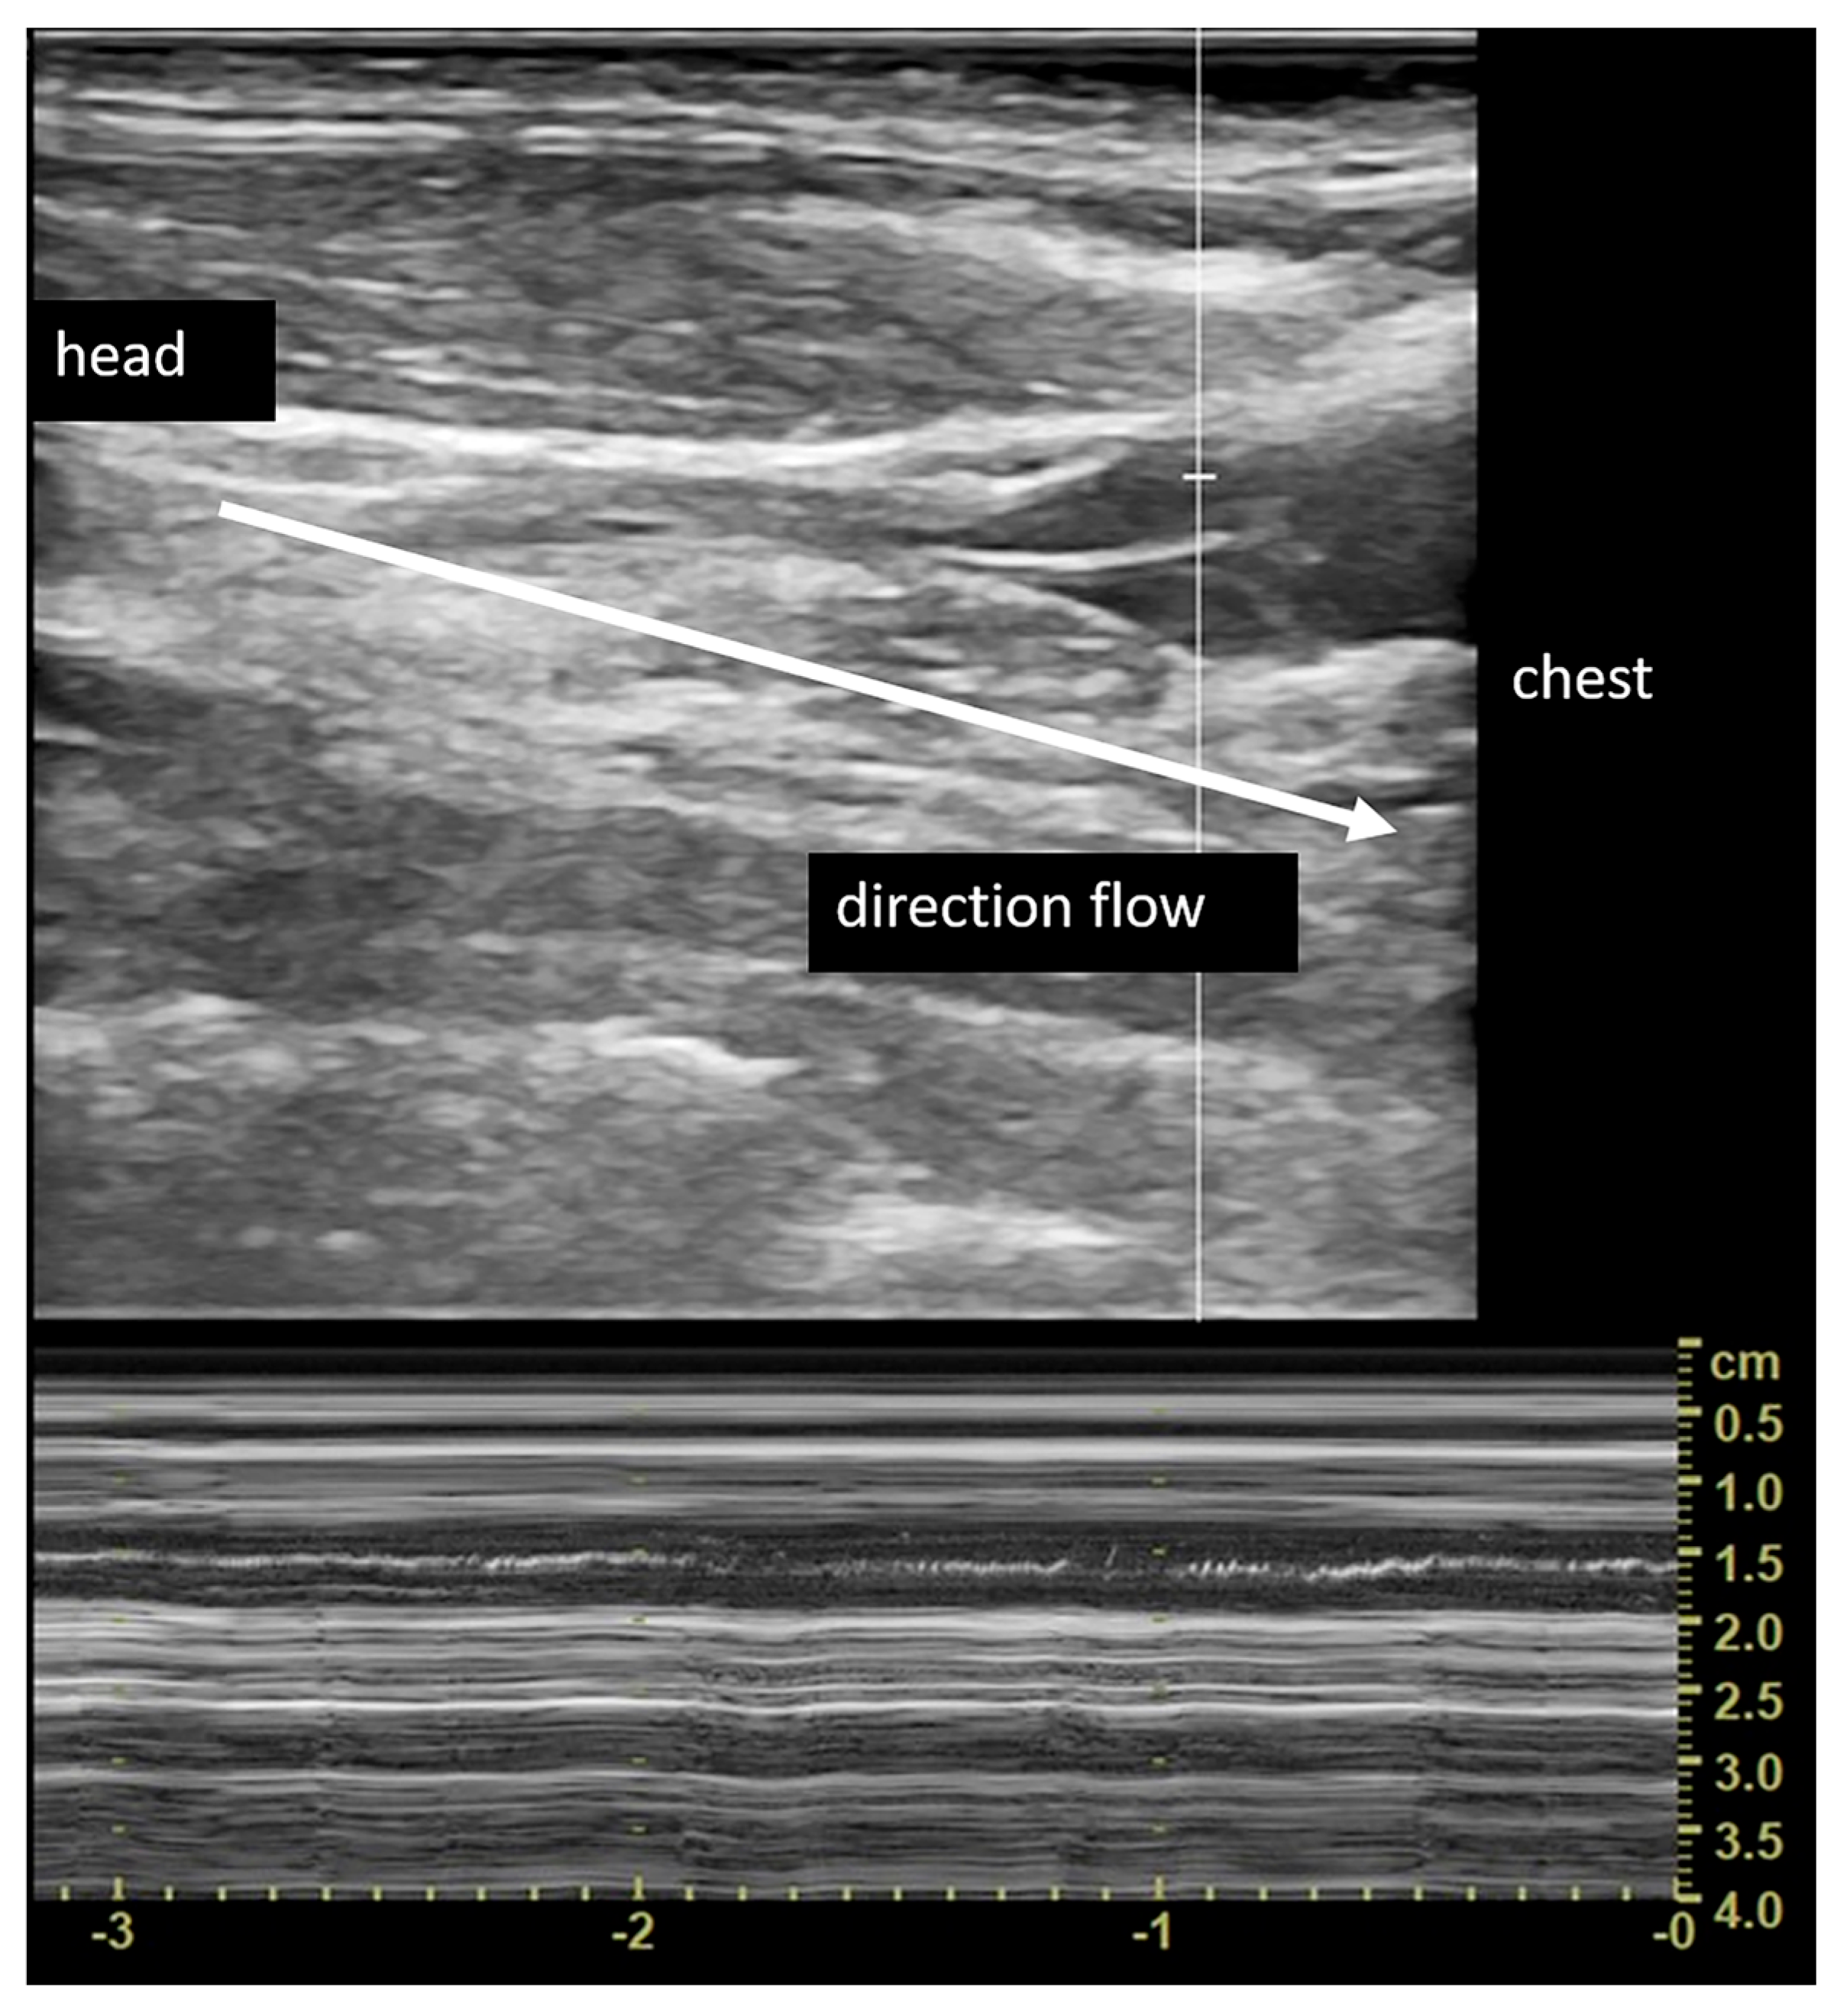

2.4. Vascular Assessment